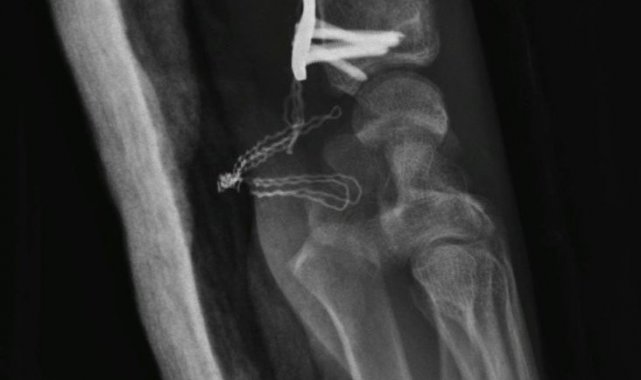

"Beş gün entübe edildi. Ne olacağı belli değildi çıkmama ihtimali vardı. Şükürler olsun doktorlarımız ve Rabbim sayesinde entübeden çıktık. Hatta ciğerin birisinde infilak vardı; ciğer sorunumuzdan dolayı özellikle yoğun bakımda entübediydik. Beş günün sonunda ciğerleri toparlamaya başladı; entübeden çıkarttılar. Solunumu normale döndü. Sırayla sağlığı yerine gelmeye başladı. Bir hafta sonra kolundan ameliyat oldu platin koydular. Omurilikten ameliyat olduk. Omuriliğinde ilk röntgende tek kırık gördüler; üç kemiği birbirine bağlayacaklardı. Sonradan ikinci röntgende üç kırık olduğunu gördük; yedi kemiği birbirine bağladılar. Omuriliğe platin takıldı. 14 tane civatamız var. Şükürler olsun doktorlarımıza, Allah razı olsun. Evladımız gayet iyi, sağlıklı, yerinde. Artık işte suratta, çenede, burunda, elmacık kemiklerinde parçalı kırıklarımız var. Osman Gazi Fakültesi'nde Allah'ın izniyle buradaki hocalarımıza, önce Rabbim'e sonra hocalarımıza emanet çocuğumuz. İnşallah daha iyi olacağız; ben kendi adıma söylüyorum. Çocuğuma, her motora bindiklerinde sürekli kask ve montlarını giymelerini tembihliyordum. Giymediklerinde fırça atıyordum. Eskişehir'de birçok yerde tanınırız, tanırlar. Sevenimiz, eşimiz, dostumuz çok; uyarırlar, telefon gelir, haber verirler. Her duyduğumda, gördüğümde söylerim. Sağ olsun, çocuğum da o gün beni dinlemiş, kaskını takmış. Şükürler olsun ki takmış; takmasaydı o gün, o kazada belki çocuğumuzu kaybederdik."